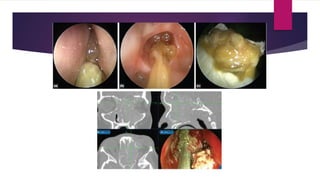

 visible fungal colonization of mucus crusts seen within the nose and paranasal sinuses on

nasoendoscopy.

Fungal ball

 dense accumulation of extramucosal fungal hyphae, usually within one sinus, most

commonly the maxillary sinus.

 diagnosis

 radiological findings

 sinus opacification often with areas of

hyperattenuation

 cheesy or clay-like debris within the sinus

 accumulation of fungal hyphae without

evidence of tissue fungal invasion seen

microscopically

 non-specific chronic inflammation of the

sinus and the absence of eosinophil

predominance, granuloma or allergic

mucin

 hallmark of AFRS is the presence of

allergic mucin.

 Grossly, it is thick, tenacious and highly

viscous in consistency.

 Hence, the terms ‘peanut butter’ and

‘axle-grease are often used to

describe the characteristic appearance

of the mucus.

 Histologically, allergic mucin consists

of an eosinophilic mucin with necrotic

eosinophils, inflammatory cells,

Charcot-Leyden crystals (the by-

product of eosinophil) and fungal

hyphae.